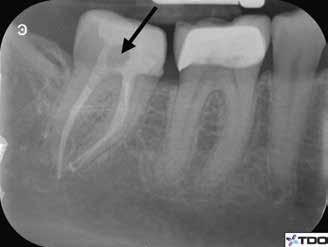

CÉLZOTT ENDODONCIAI MIKROSEBÉSZET

1. a-n. ábrák: Preoperatív CBCT-felvétel a bal alsó 6-os (3.6) fogról. Az axialis (a), coronalis (b) és sagittalis (c) nézeteken a mezialis és distalis gyökerek apicalis harmada körül sugáráteresztő zóna és ép buccalis corticalis csont látható. Egy olyan sablont terveztünk, amely jelezte a csontablak határait az apicalis terület pontos elérése érdekében (d). A mikrosebészeti bevatkozás során a sablont a helyére illesztettük (e), a csontablak határait megjelöltük (f) egy Piezotome CUBE LED kézi-darabba fogott fűrésszel, majd kivágtuk és eltávolítottuk (g és h) az apicalis területhez történő hozzáférés, illetve a mezialis és distalis gyökerek rezekciójának, retrográd preparációjának és retrográd gyökértömésének elvégzése érdekében (i). Végezetül a csontablakot visszaillesztettük és kollagén szivaccsal stabilizáltuk (j). A műtét után közvetlenül készített röntgenfelvétel a 3.6-os fogról (k). A kétéves kontroll során készített CBCT-felvétel: axialis (l), coronalis (m) és sagittalis (n) nézetek.

Egy 63 éves páciens korábban már kezelt bal alsó első nagyőrlőfogából (3.6) eredő mérsékelt fájdalom miatt kereste fel rendelőnket. A kórtörténetében panasza szempontjából releváns információ nem szerepelt. Az elkészült CBCT-felvételen a korábbi kezelések során észre nem vett, jelenleg feltáratlan meziobuccalis csatornát, valamint a mezialis és distalis gyökerek körül kialakult periapicalis elváltozást, és ezt a léziót borító intakt buccalis corticalis csontlemezt láttunk.

Klinikai vizsgálat során vertikális kopogtatási érzékenységet jelzett. A fog körül mérhető szondázási mélység és a fogmobilitás fiziológiás volt. A CBCT-felvételen nem észleltünk a csontos regeneráció megindulására utaló jeleket (1. a–c. ábrák). A korábban gyökérkezelt, gyökértömött és revideált 3.6-os fog esetében az alábbi diagnózis került felállításra: periodontitis periapicalis symptomatica. A panaszokat okozó fog további ellátása során navigált endodonciai mikrosebészetet kívántunk alkalmazni. Az alsó állcsontról intraorális szkent (TRIOS, 3Shape) készítettünk, és a felszíni topográfiát tartalmazó STL fájlt, valamint a CBCT-felvétel készítése során nyert DICOM fájlokat a Blue Sky Bio szoftver segítségével egyesítettük. A sebészi sablon megtervezésére az így kapott háromdimenziós képet használtuk. A sablon kialakítása során arra törekedtünk, hogy a sablon egyértelműen meghatározza a gyökércsúcsi terület eléréséhez szükséges csontablak határait (1. d. ábra)